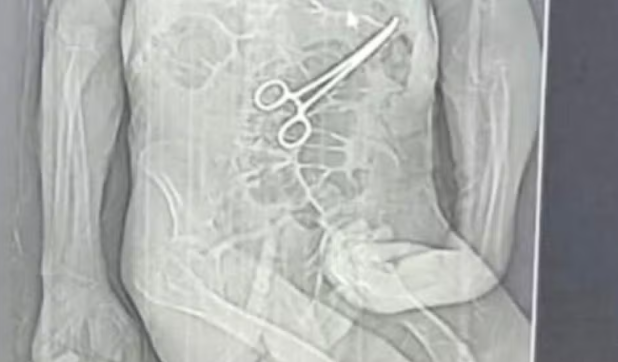

A família de Manoel Cardoso de Brito, de 68 anos, acusa o Hospital Municipal de João Pinheiro, no Noroeste de Minas, de erro médico após o idoso morrer na véspera do Natal. Segundo os parentes, uma pinça cirúrgica foi esquecida dentro do corpo do paciente após a primeira cirurgia, fato que, segundo os familiares, só veio à tona depois do óbito.

Segundo o advogado da família do idoso, Iuri Evangelista Furtado, as medidas legais começaram a ser adotadas depois que um exame de tomografia, divulgado por uma rádio local, chegou ao conhecimento de parentes. A imagem indicaria a presença do instrumento cirúrgico no corpo do paciente.